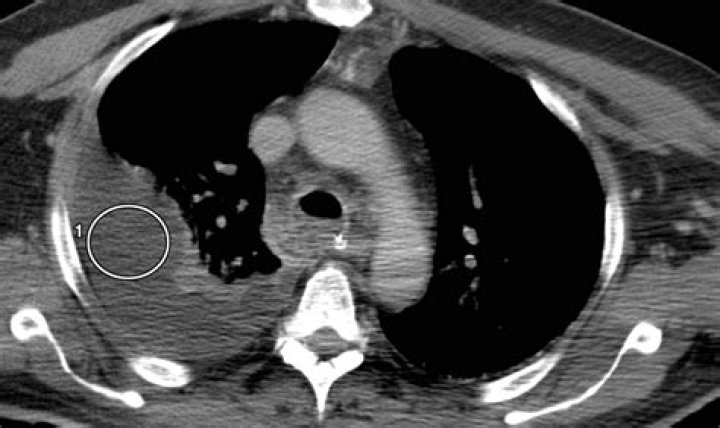

Thoracentesis and pleural fluid analysis are the criterion standards to establish a diagnosis of chylothorax. Alternatively, in a postsurgical patient, tube thoracostomy output can be analyzed. Pleural fluid analysis for triglyceride content helps to confirm the diagnosis of chylothorax.

Chylothorax is a rare condition that results from thoracic duct damage with chyle leakage from the lymphatic system into the pleural space, usually on the right side. It has multiple aetiologies and is usually discovered after it manifests itself as a pleural effusion.